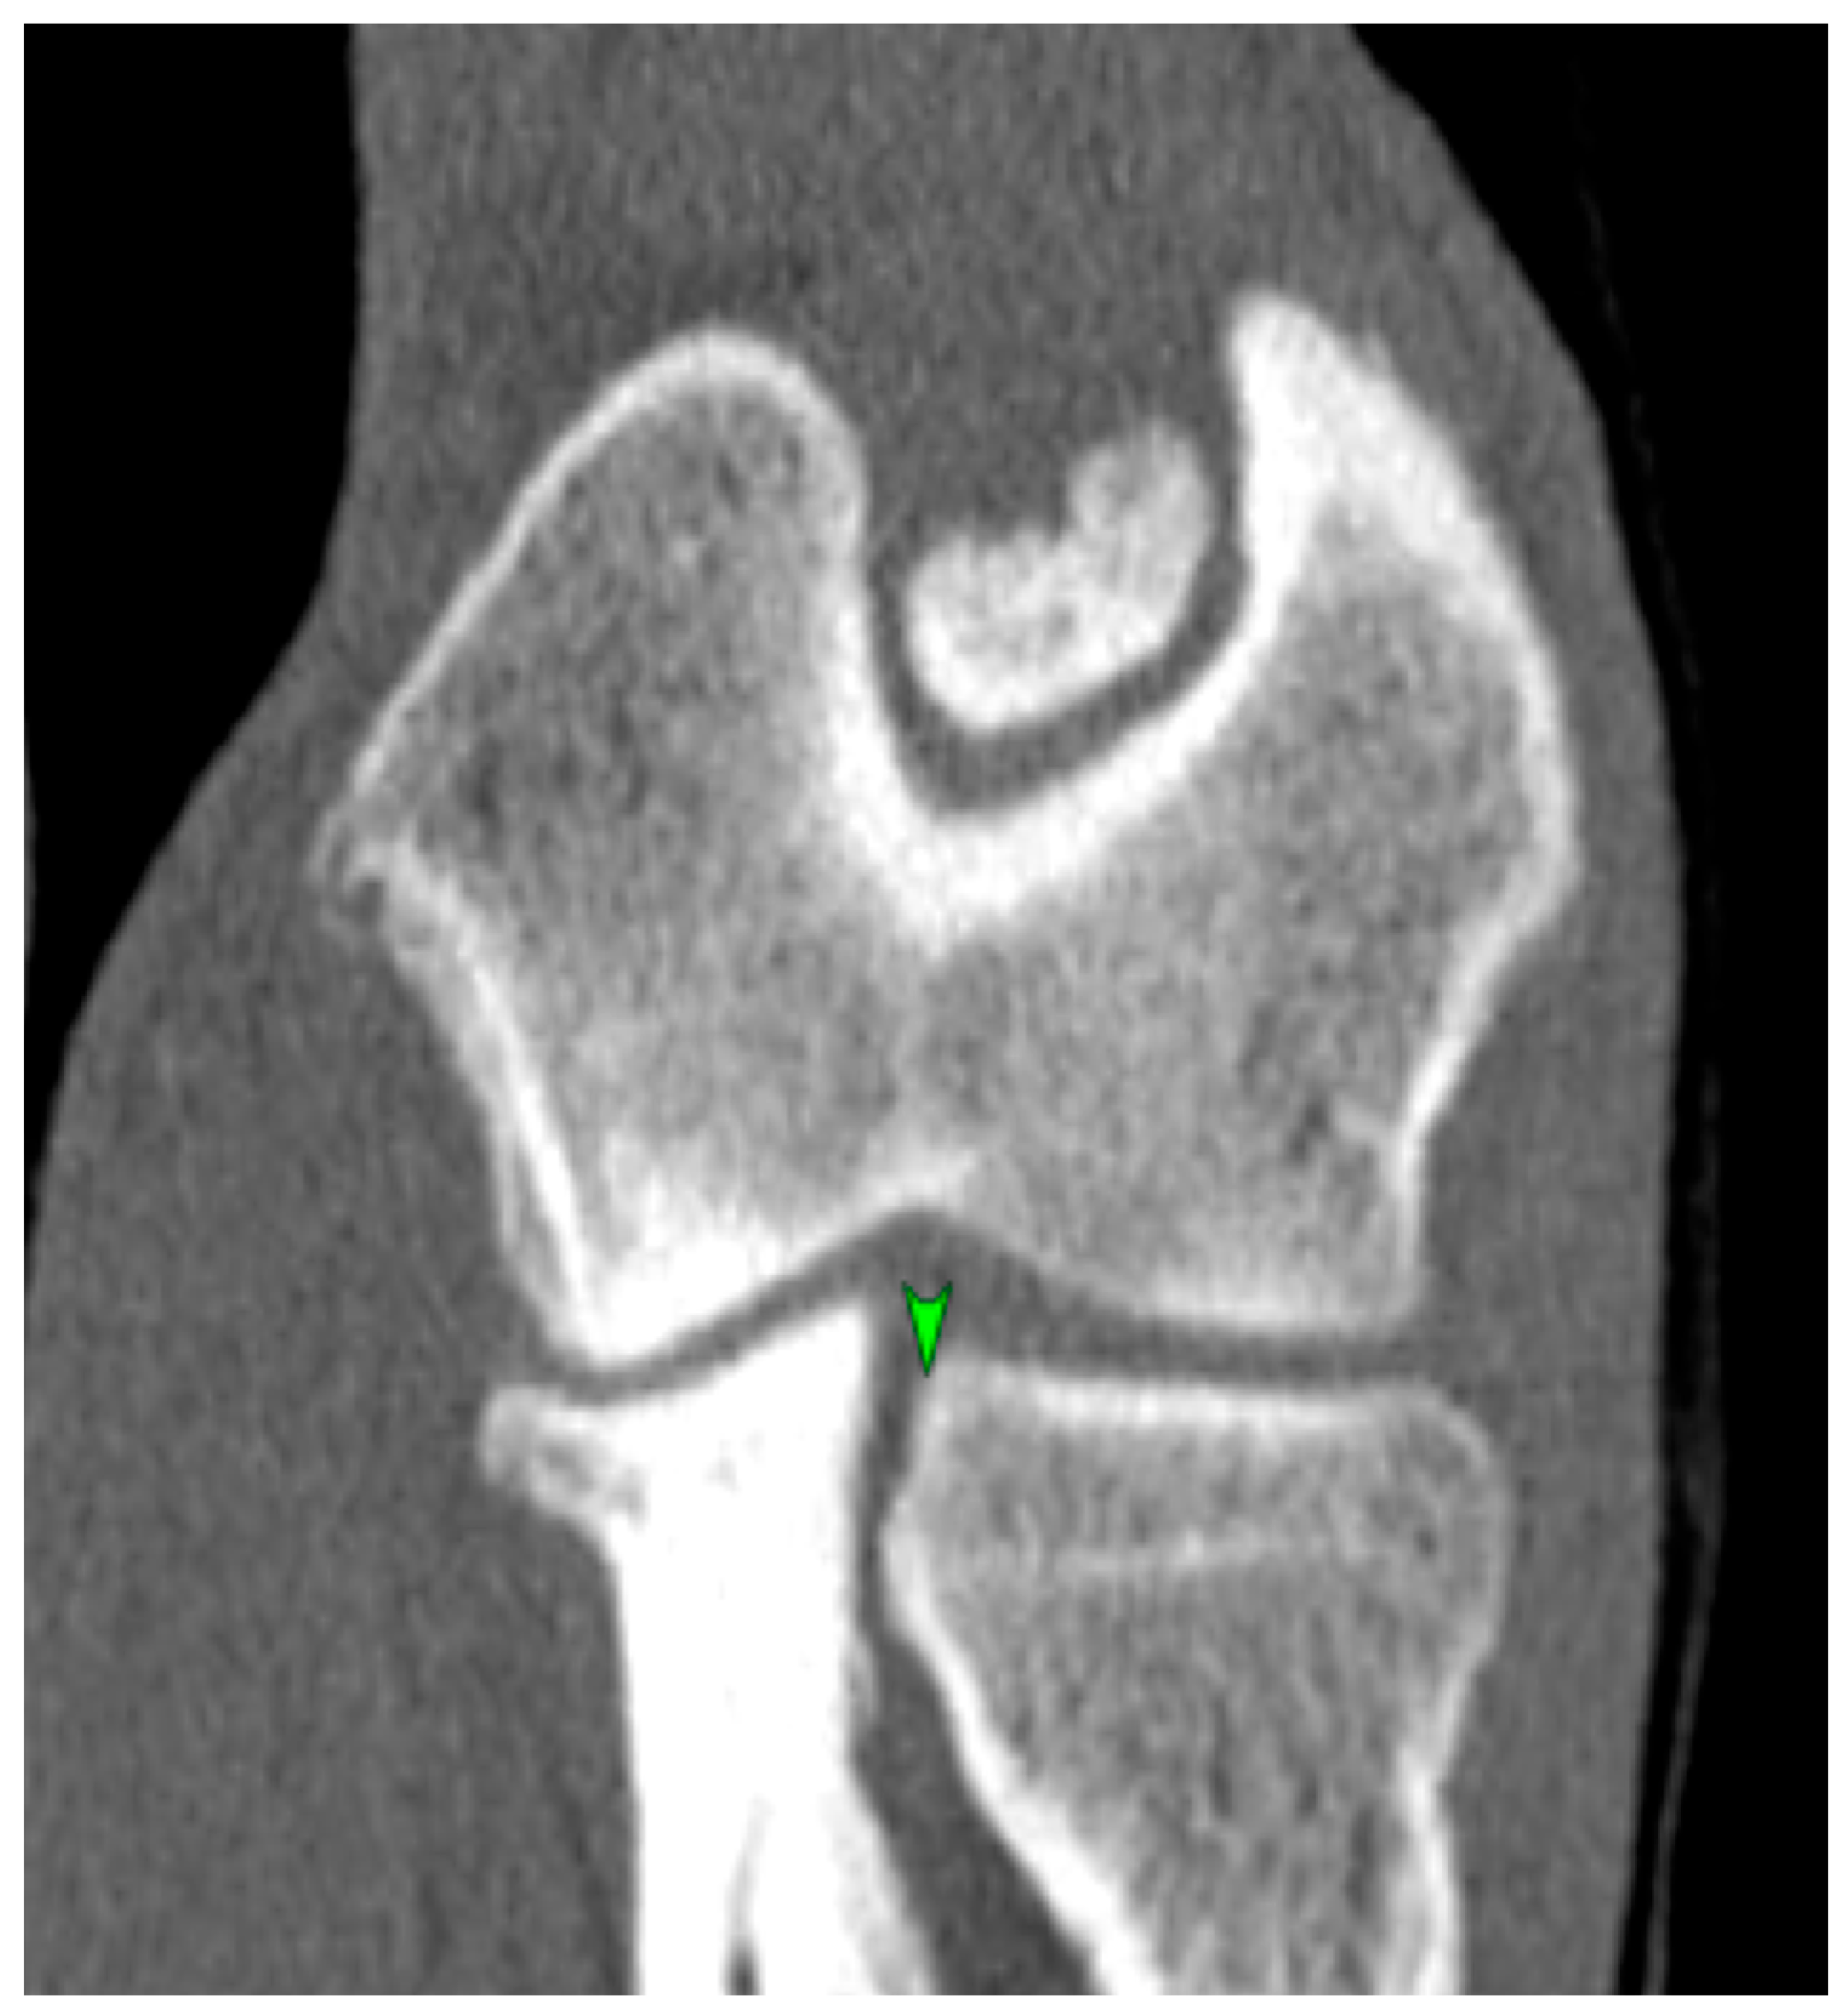

2.4. CT Technique

2.5. Measurement Techniques